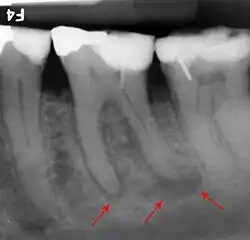

If disease is identified through this process, then a full periodontal analysis is performed, often by dental hygienists, oral health therapists, or specialist periodontists. This involves full mouth periodontal probing and taking measurements of pocket depths, clinical attachment loss and recession. Along with this other relevant parameters such as plaque, bleeding, furcation involvement and mobility are measured to gain an overall understanding of the level of disease. Radiographs may also be performed to assess alveolar bone levels and levels of destruction.[40]

- ^ Severity: Interdental clinical attachment level at site with greatest loss; Radiographic bone loss and tooth loss.

- ^ Complexity of management; Probing depth, pattern of bone loss, furcation lesions, number of remaining teeth, tooth mobility, ridge defects, masticatory dysfunction.